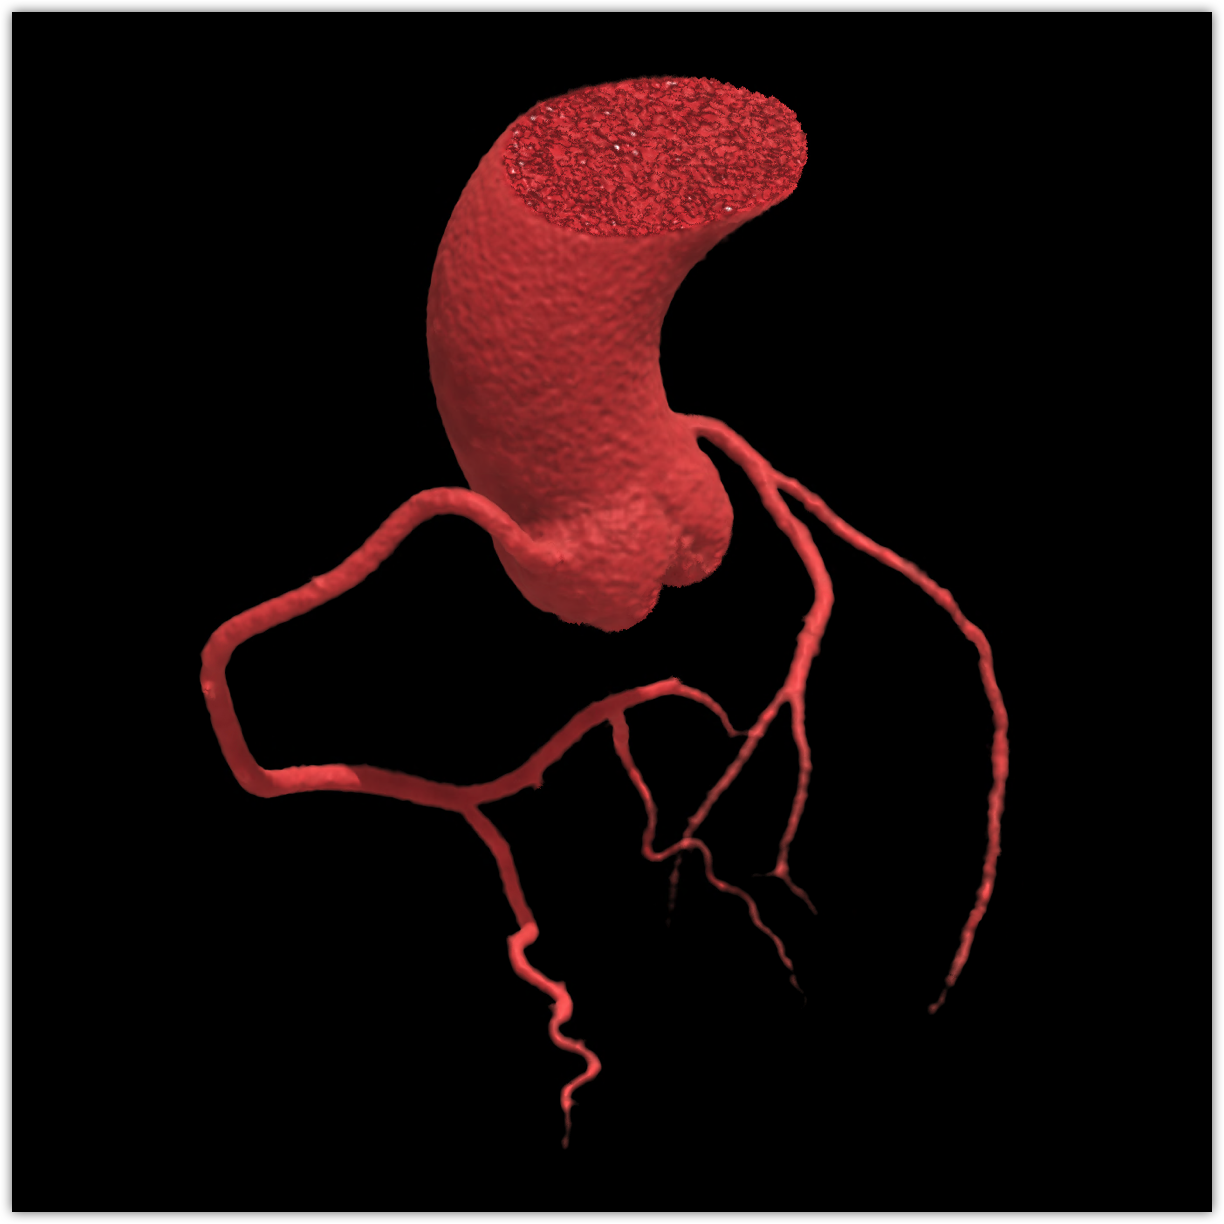

We believe in keeping you as healthy as possible. One of the ways we do this is by checking for heart disease with a Coronary CT Angiogram (CCTA) — a non-invasive scan that can see disease in your heart vessels even if you have no symptoms.

Most people have no symptoms until it’s too late. A Coronary CT Angiogram (CCTA) lets us see disease in the vessels of your heart — before a heart attack happens.

Coronaries scan